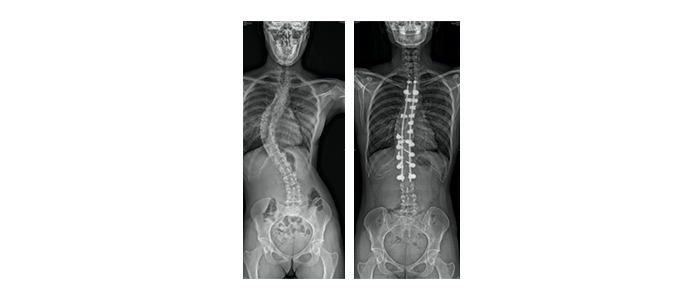

L’objectif de l’intervention est de stopper le processus d’aggravation de la scoliose, et si possible de redresser la colonne vertébrale à des valeurs normales pour lui redonner un bon équilibre. Chez un adolescent, le chirurgien bloque définitivement les vertèbres concernées par des tiges, des vis, ces crochets et autres instrumentations en titane. Une greffe osseuse est pratiquée afin de solidifier le tout. Il est impératif de choisir un centre spécialisé dans la chirurgie du rachis de l’enfant. L’intervention réclame en effet un savoir-faire spécifique, une équipe entraînée et un plateau technique particulier, notamment une surveillance de la moelle épinière assurée à l’aide d’un équipement de surveillance adapté.

Sur la radiographie de droite, on observe les matériels de fixation qui ont permis de redresser la colonne vertébrale

Malgré la fixation de la colonne vertébrale visible sur la radiographie de droite cette jeune fille récupère une mobilité proche de la normale dans les disques vertébraux laissés libres ainsi que le bassin et les hanches

Clichés de la même jeune fille avant et après l’intervention